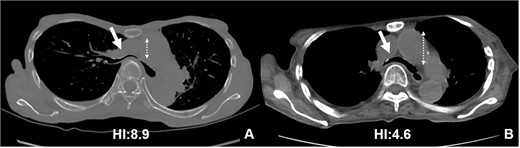

CT scans are used to monitor changes over time. In (A), chest CT findings of severe PE with stenosis of the right main bronchus. The trachea, which was centrally located on CT scan 8 years ago (2B), has shifted to the left now (2A). Additionally, the CT-HI worsened over his 8 years, increasing from 6.8 to 8.9.

The patient was a 74-year-old woman with a history of childhood PE. Fourteen years ago, a total glossolaryngectomy was performed at another hospital for oropharyngeal cancer, and a permanent tracheal stoma was created. Approximately 2 years later, the patient gradually experienced difficulty in breathing. Chest computed tomography (CT) revealed severe PE and right main bronchial stenosis. Subsequently, the patient was referred to our department. A preoperative spirometry test showed a vital capacity of 1.14 L (45% of the predicted value). As part of the imaging test, a chest CT indicated a leftward deviation of the trachea. Symmetrical depression with a Haller Index (HI) of 8.9 and stenosis of the right main bronchus were observed at the same site (Fig. 1). The chest CT taken over 8 years indicated that the leftward deviation of the trachea had progressed and the thoracic depression had worsened (Fig. 2). Intraluminal observation using a bronchoscopy revealed severe stenosis of the right main bronchus, making peripheral observation challenging (Fig. 4A).